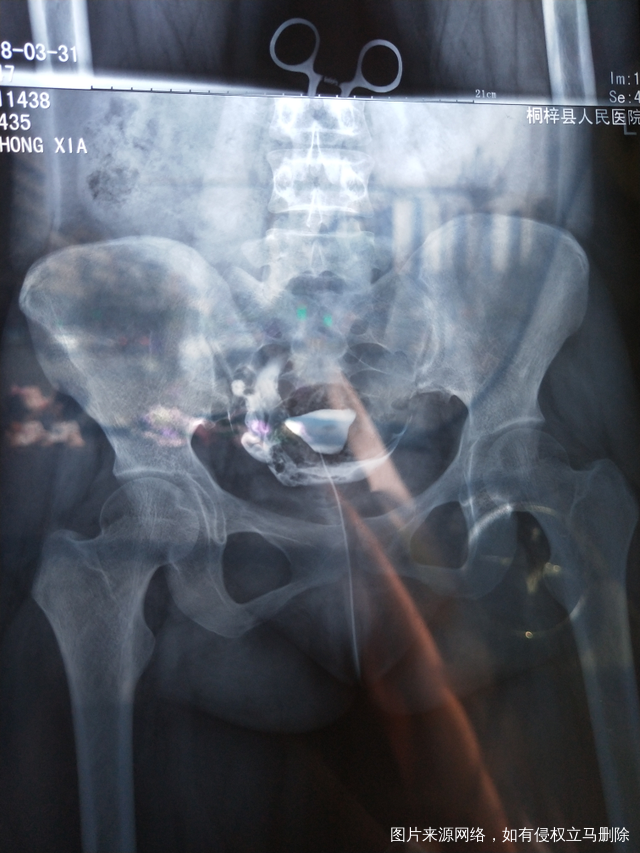

医生 看看我的输卵管造影